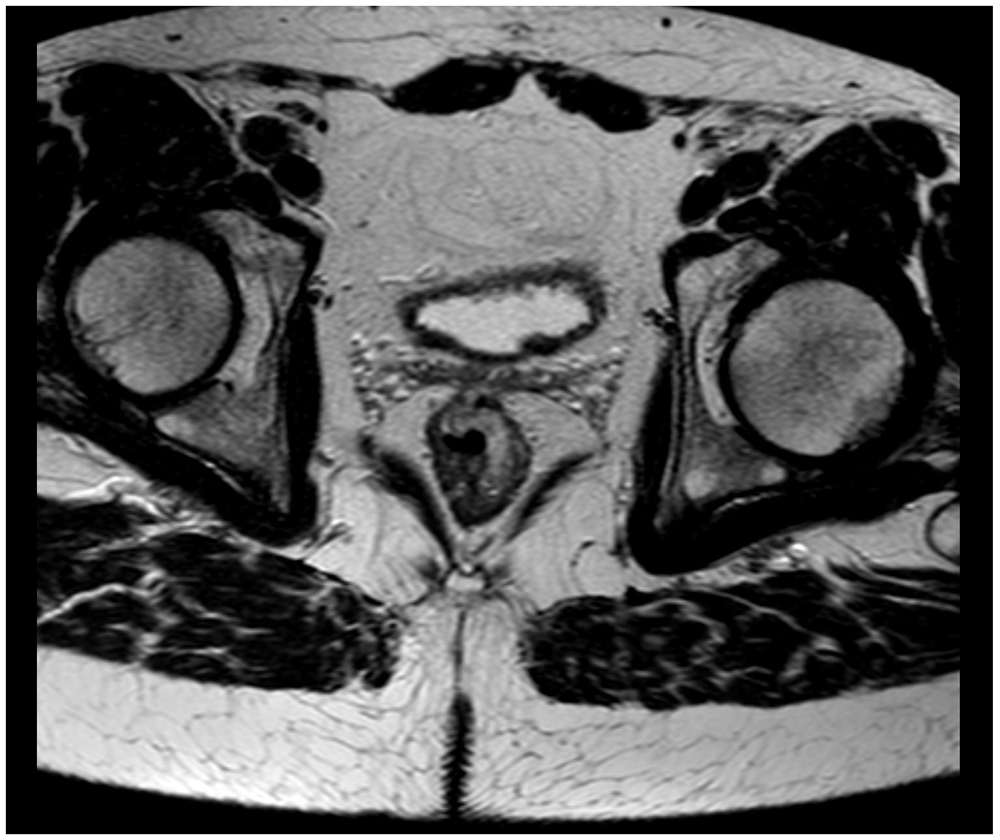

A 58-year-old Caucasian man with no prior medical or surgical history was admitted to the emergency department after referral from his general practitioner. The patient complained of constant diffuse abdominal pain for two days with exacerbation upon movement. He had had fever for one day. His stool was normal without blood and there was no nausea or vomiting. The patient had no family history of colorectal cancer. The abdominal examination revealed direct tenderness in both lower quadrants. The DRE that was performed by the newly qualified doctor on call was without palpable tumors. Laboratory blood tests showed elevated C-reactive protein (110 mg/L [normal value less than 3 mg/L]). All other blood tests were normal. An acute computed tomography (CT) scan of the abdomen showed signs of acute appendicitis. A diagnostic laparoscopy confirmed the diagnosis macroscopically and an uncomplicated laparoscopic appendectomy was performed. The patient was discharged the following day. The postoperative standard histopathologic examination of the appendix showed acute non-perforated appendicitis and, surprisingly, a 13 mm T1 goblet cell adenocarcinoma in the apex of the appendix with tumor-free resection margins. The patient was informed and underwent a new CT scan of the thorax and abdomen. The only new finding on the repeated CT scan was rectal wall thickening. The patient was discussed at a multidisciplinary team conference where it was decided to perform a colonoscopy due to the rectal wall thickening and thereafter a laparoscopic right hemicolectomy due to the tumor in the appendix. Prior to the colonoscopy, the endoscopist, who is an experienced colorectal surgeon, performed a DRE. The endoscopist palpated the distal part of a tumor in the anterior wall of the rectum seven centimeters from the anal opening. The colonoscopy showed a tumor highly suspicious for malignancy with a central depression of 25 mm (Figure 1). It was classified as National Institute for Clinical Excellence (NICE) type 3. A magnetic resonance imaging (MRI) scan staged the tumor as a T2 without metastasis to lymph nodes or distant metastasis (Figure 2). The histopathologic examination of the rectal lesion showed a primary signet ring cell carcinoma that was histologically distinct from the appendiceal tumor. Hence, the patient had two primary synchronous tumors. Eventually, the patient was treated with simultaneous laparoscopic right hemicolectomy and low anterior resection. Figure 3 presents a timeline of the events. The postoperative course was complicated by an anastomotic leakage of the colorectal anastomosis. The leakage was treated with endoscopic vacuum-assisted closure. After surgery, the patient received adjuvant chemotherapy.

Figure 1. Colonoscopy showing the rectal tumor.